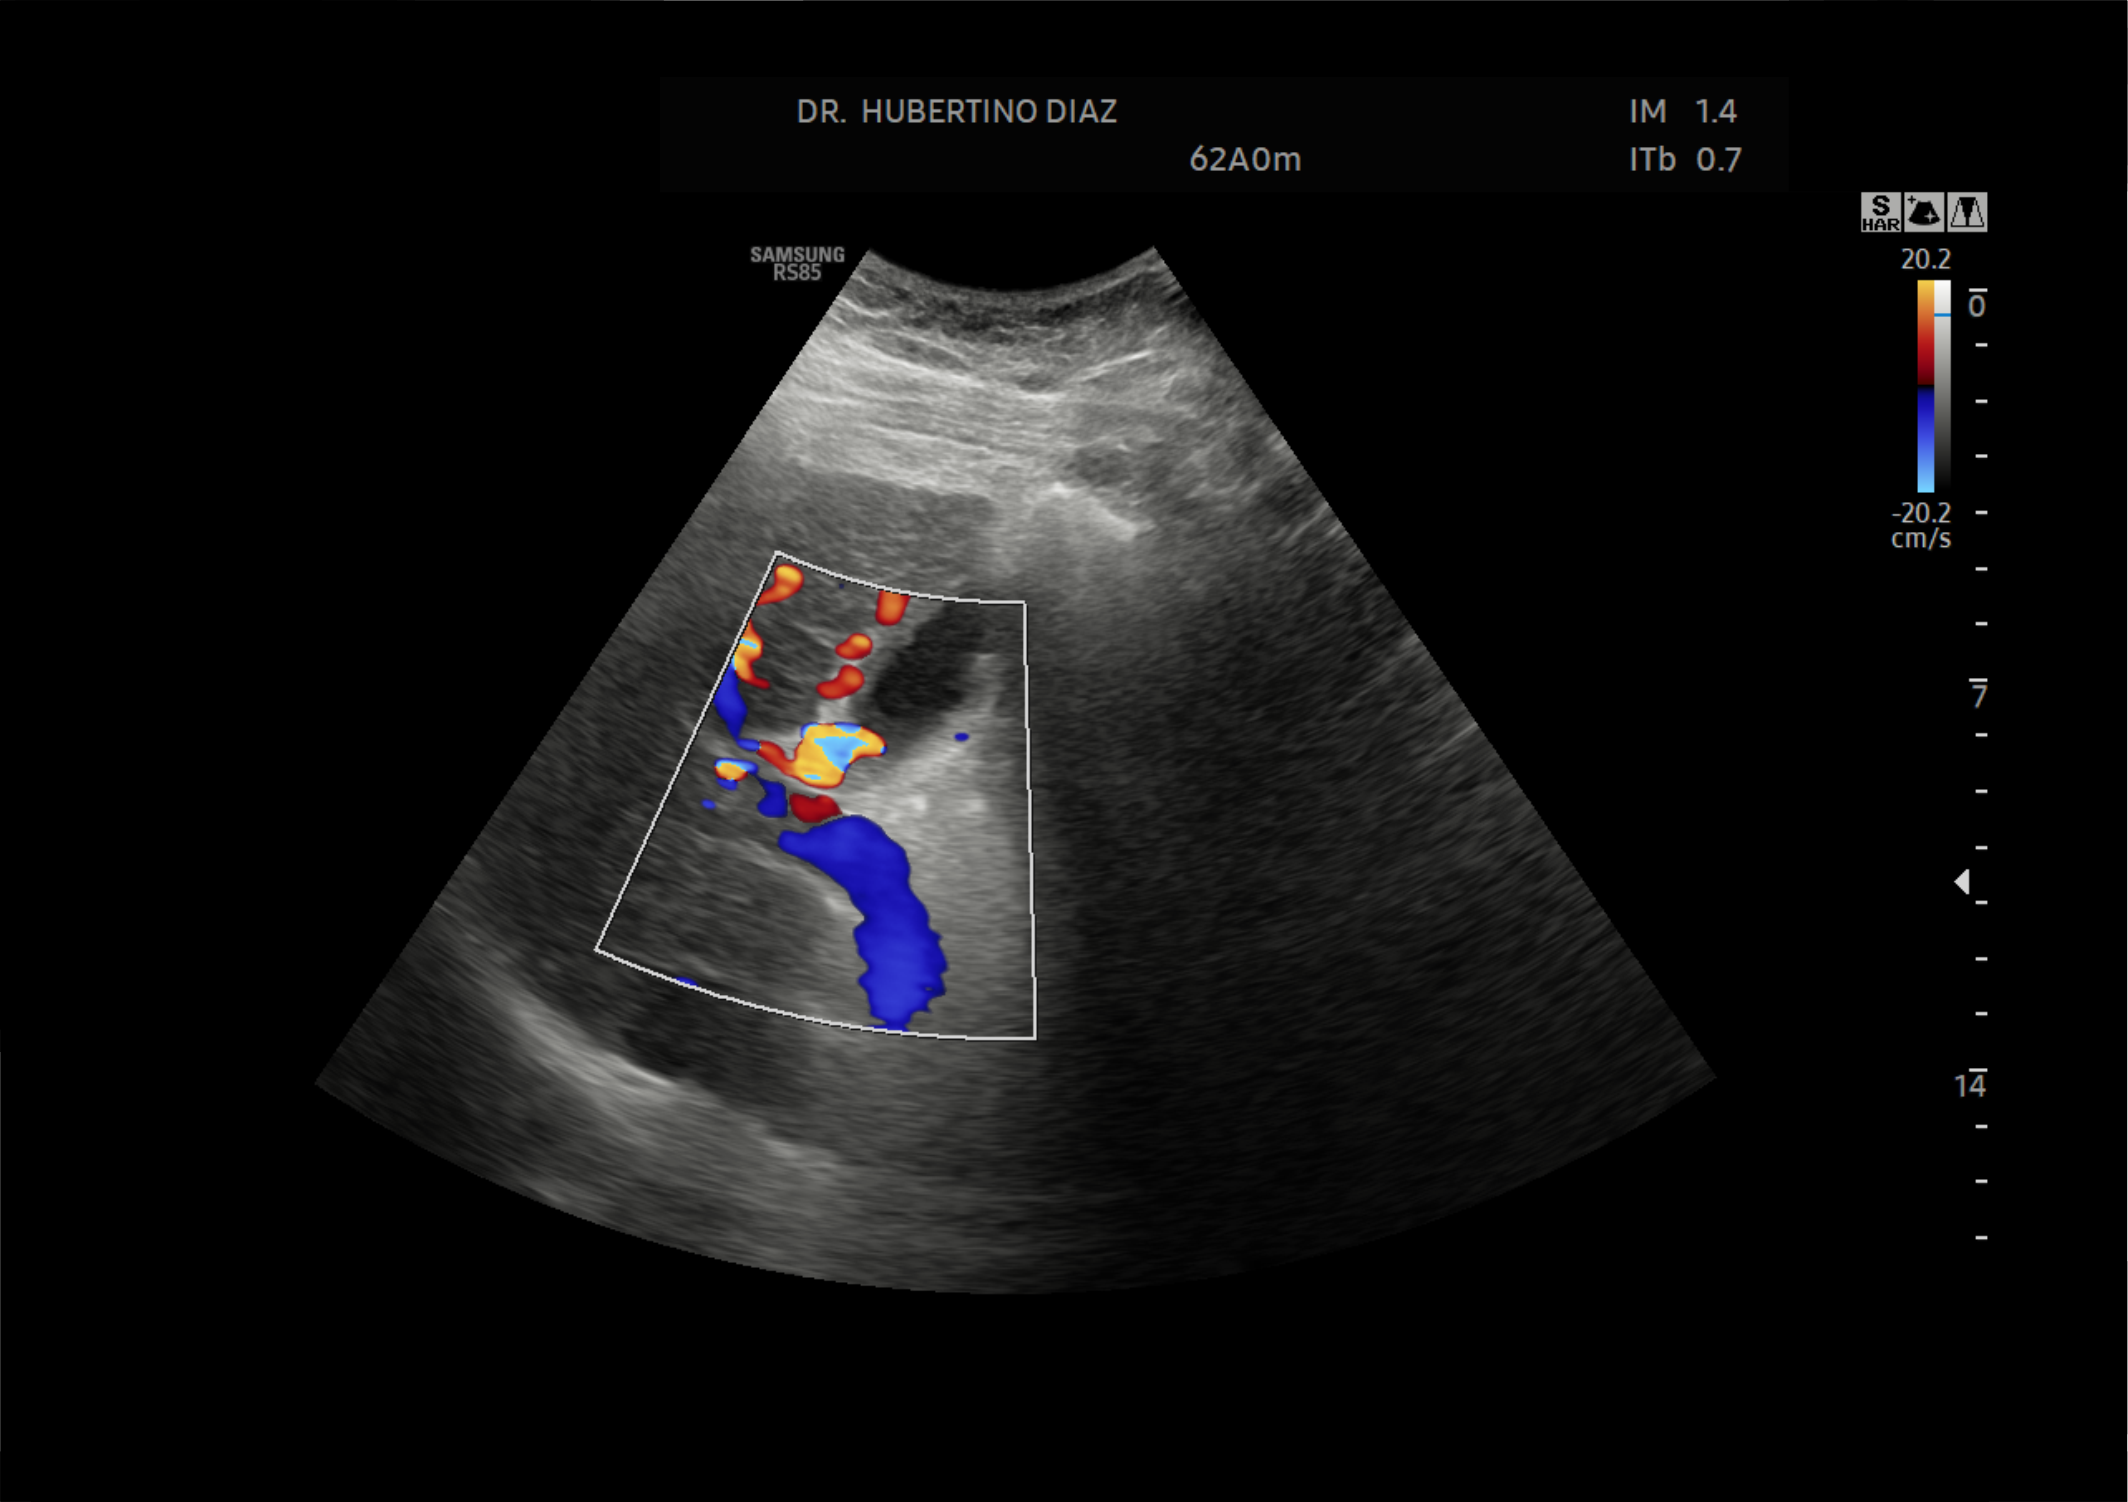

Ecografía Doppler color de cavernomatosis de vena porta.

El objetivo del estudio Doppler de hígado es valorar la morfología y la hemodinámica de los vasos hepáticos, determinar la dirección, el volumen, la velocidad del flujo y la presencia de colaterales. Determina: hipertensión portal, trombosis portal, malformaciones vasculares, insuficiencia cardiaca congestiva, aneurismas, pseudoaneurismas, varices y entre otros.